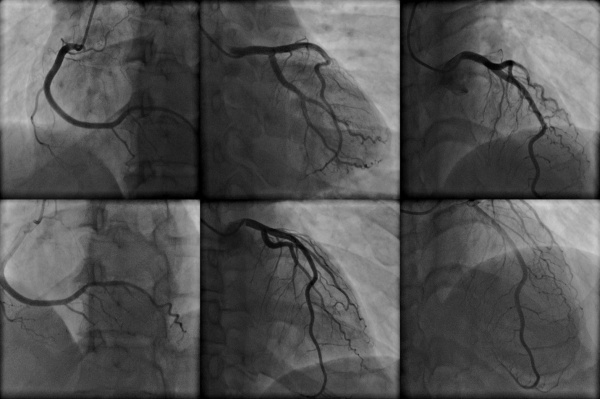

Оптимальное время коронарной ангиограммы для пациентов с хроническим заболеванием почек.

Хроническая болезнь почек (ХБП) связана с повышенным риском прогрессирования ишемической болезни сердца (ИБС).

Распространенность ИБС возрастает по мере ухудшения функции почек даже на ранних стадиях нарушения функции почек. Однако данных о связи между тяжестью ИБП и продолжительностью ХБП немного.